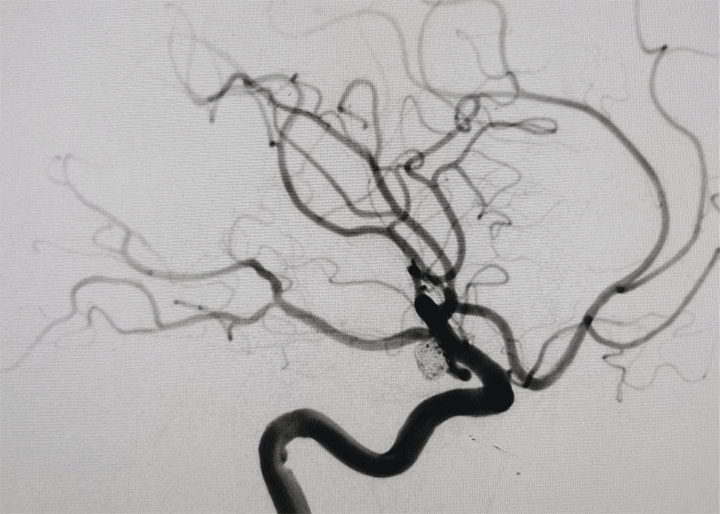

神经外科介入团队在张德辉院长的带领下,迅速启动救治方案,与患者家属充分沟通交流病情,告知患者血管条件差,手术中,医生们面临着巨大挑战,患者血管呈II型弓且迂曲严重,手术难度极高,导管到位困难,若双侧动脉瘤同时处理,手术风险极高,尽量争取一次手术解决双侧动脉瘤。

手术中造影可见右侧动脉瘤破裂小泡,为责任动脉瘤,术中予以支架辅助栓塞,考虑患者血管条件极差,若左侧同期处理,手术时间较长,容易形成血栓,增加手术风险,团队决定先处理责任动脉瘤,左侧后交通动脉瘤择期处理。

经过3个月的精心调养,患者身体恢复良好,患者及其家属对神经外科极其信任,此次重返东方总院,是为了处理左侧的未破裂动脉瘤。尽管这是一次择期手术,但神经外科团队丝毫不敢懈怠,术前进行了全面评估和周密的手术规划。

手术过程顺利,医生们凭借丰富的经验和精湛的技术,成功完成了左侧动脉瘤的处理,手术栓塞效果令人满意。由于是未破裂动脉瘤,患者恢复速度较快,术后仅3天就达到出院标准。